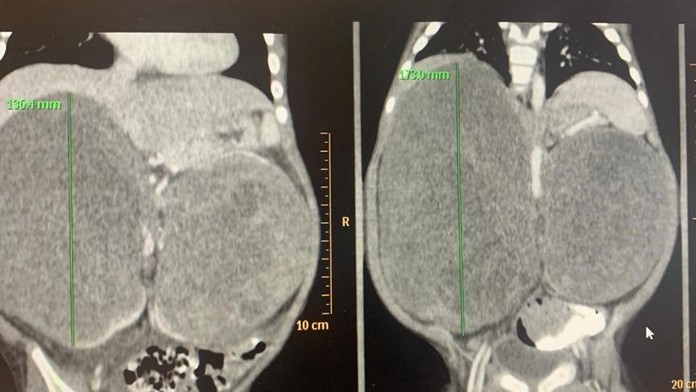

Lekári Národného ústavu detských chorôb (NÚDCH) chlapčekovi odstránili dva veľké obojstranné nádory na obličkách. Jeden z nich vážil 1,3 kilogramu a pacientovi tlačil na bránicu a pľúca. Lekárom sa podarilo zachrániť aj obličku. Informovala o tom hovorkyňa NÚDCH Dana Kamenická.

Po konzultáciách so zahraničnými špecialistami v Holandsku a USA sa ukázalo, že je nutné zrealizovať vysoko náročné a rizikové operácie. "Na CT vyšetrení sme videli obojstranný veľký nádor na obličke, ktorý tlačil na bránicu a boli utláčané pľúca. Dieťatko už začínalo mať problémy s dýchaním. Rozhodli sme sa pre urgentnú operáciu," ozrejmil riaditeľ NÚDCH a operujúci lekár Peter Bartoň.

Po úspešnej operácii má detský pacient všetky obličkové parametre v poriadku. "Táto operácia bola pre nás skutočnou chirurgickou výzvou, akú radi prijímame. Išlo o operáciu na hranici technických možností s neobvykle komplikovanou rekonštrukciou zvyšku obličky po odstránení tumoru," dodal prednosta kliniky pediatrickej urológie Ján Breza.